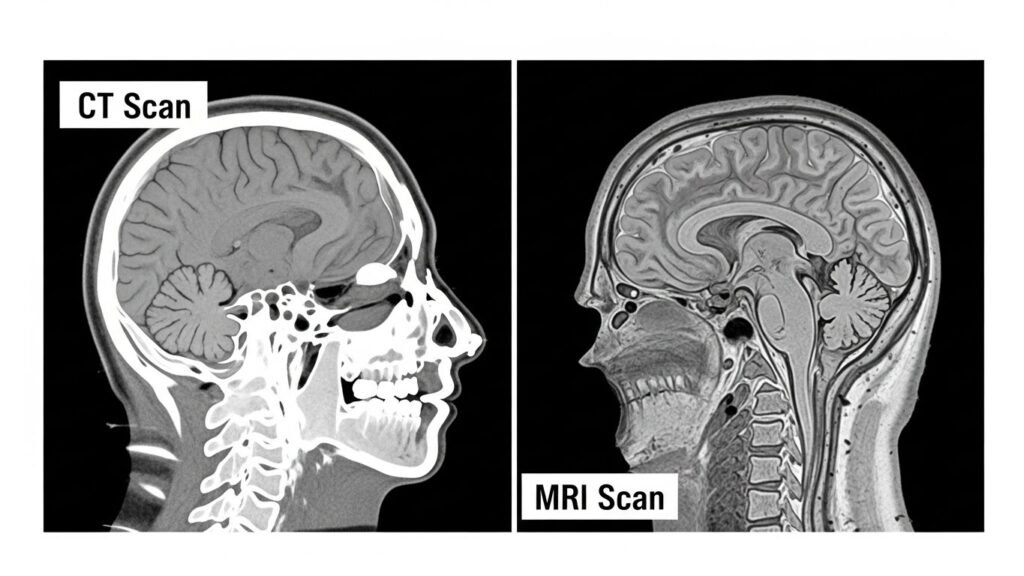

CT Scan vs MRI Images: What You Actually See

CT images highlight:

- Bones

- Air cavities

- Sharp edges

MRI images show:

- Muscles

- Ligaments

- Organ layers

It’s not about which looks nicer. It’s about solving a puzzle.